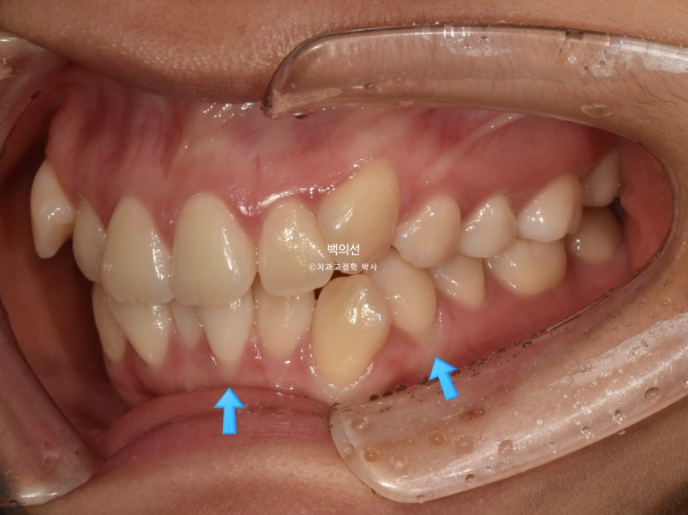

23년 7월 교정을 위해 내원한 환자분입니다.

덧니가 심한 편 입니다.

잇몸이 얇아서 20대 초반의 나이임에도 불구하고 덧니를 포함한 일부 치아의 잇몸이 내려가 있습니다.

군데군데 잇몸이 내려가 뿌리 노출된 부분들이 있습니다.

덧니 펼 공간이 많이 필요하고 잇몸도 얇아 비발치로 치료 시 잇몸이 더 내려갈수도 있는 상태입니다.

초진 입매를 보면 입술돌출은 거의 없지만 상기의 이유로 작은어금니 4개 발치교정을 결정하였습니다

환자분은 치주건강상의 이슈로 발치의 이유는 납득을 하지만 발치로 인해 입이 너무 들어가지 않게 해달라고 요청하셨습니다.